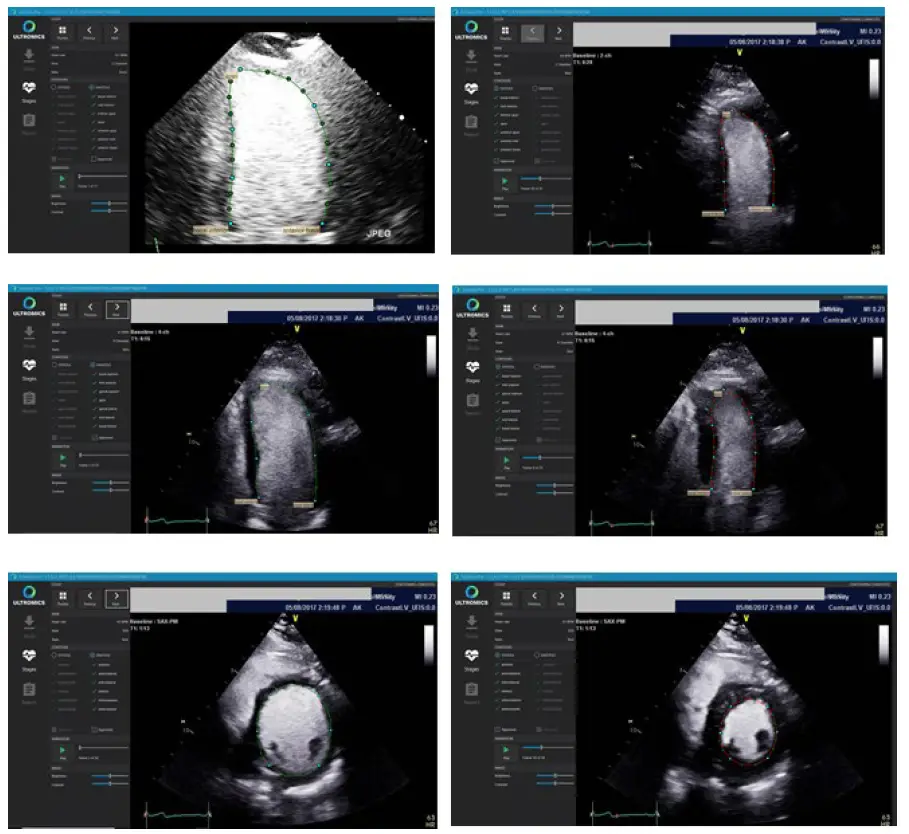

If a batch of received files pass the technical QC, the algorithm for automated contour detection of the endocardium of the LV (ROI’s) is applied. The auto-contouring is detected at end-systole (ES) and end-diastole (ED) for the apical two chamber (A2C), four-chamber (A4C) and mid-ventricular SAX views at both rest and peak stages. Appendix A provides examples of contours that shall be rejected and accepted.

Figure 2: Example of the contouring screen used to access the quality of the generated auto-contours

Contour Images: Accept

Contour Images: Reject